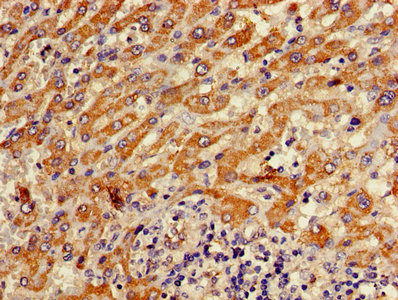

Immunohistochemistry of paraffin-embedded human liver cancer using CSB-PA002355HA01HU at dilution of 1:100